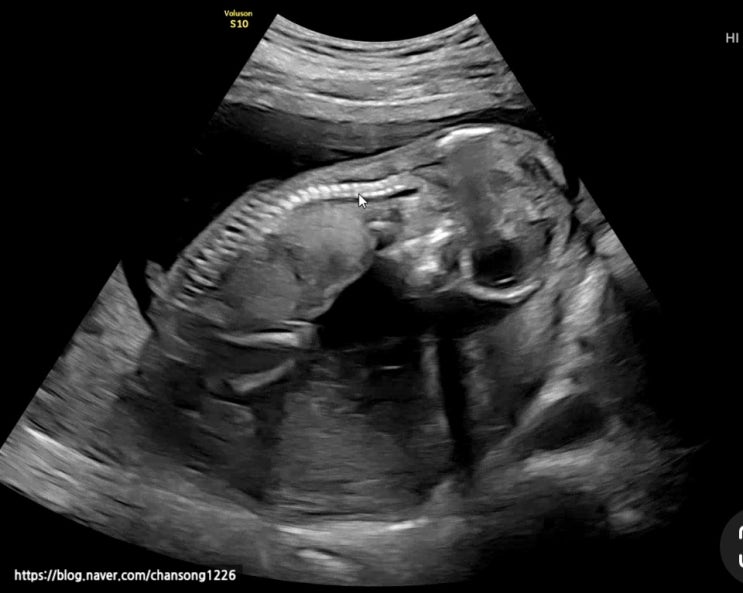

임신중기 12주 15주 16주 초음파 성별확인 1차 기형아 검사 태동시기

저의 임신중기 초음파와 증상에 대해 기록하고자 합니다. 성별확인과 1차 기형아 검사, 그리도 태동에 대한...

임신초기 7주 8주 9주 임신증상 및 입덧과 초음파

사람마다 주수별 임신 증상은 천차만별이겠지만 저의 경우의 임신증상에 대해서 기록해 보고자 합니다. 전...